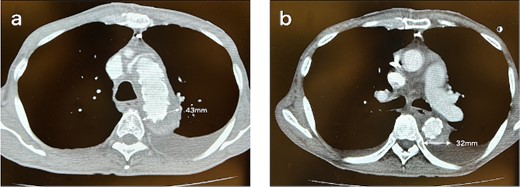

A 62-year-old male presented at the previous hospital with left hemiplegia. Computed tomography (CT) detected an aortic dissection with malperfusion of the right brachiocephalic artery, necessitating a referral to our institution. Preoperative CT showed the primary entry tear in the distal aortic arch and a patent false lumen. A total arch replacement was successfully performed using the fenestrated FET technique. The surgical procedure involved median sternotomy, establishment of extracorporeal circulation with right atrial drainage and perfusion via right axillary artery, circulatory arrest at 28°C and selective cerebral perfusion to perfuse all cervical vessels. Myocardial protection was provided by retrograde cardioplegia. Following resection of the aorta at zone 1, FET was inserted and deployed into the aorta, perfusing blood from the femoral artery. Fenestration of the graft at the ostium of the second and third cervical branches was performed. A U-shaped graft was placed around cervical branches, and three 4-0 polypropylene U-shaped sutures were roughly placed to fix the open stent graft, leaving some gaps between the sutures. Subsequent procedures included anastomosis of a four-branch graft to the distal aorta, reconstruction of the brachiocephalic artery and proximal anastomosis. Postoperative contrast-enhanced CT on day 5 showed no endoleak and favorable remodeling of the descending aorta (Fig. 1). However, after 6 months, follow-up CT detected a fenestration-related endoleak and an enlarged aortic arch (Fig. 2), prompting reoperation. The reoperation involved median re-sternotomy, establishment of extracorporeal circulation with right femoral vein drainage and perfusion via an 8-mm graft anastomosed to the left axillary artery, circulatory arrest at 28°C, and selective cerebral perfusion to perfuse all cervical vessels. Upon opening the artificial graft, it was observed that the stent graft had some gap between fixed U-sutures and had become detached from the aorta, revealing a small entry adjacent to it, which communicated with the false lumen. The left subclavian artery (LSCA) was ligated, and the left common carotid artery was transected at its origin and sutured. An open stent was inserted distally, followed by placement of a felt strip and a 4-0 running suture. Subsequent procedures included anastomosis of a four-branch graft to the distal aorta, reconstruction of the three cervical branches and proximal anastomosis. The surgery was completed without complications. Postoperative contrast-enhanced CT on day 5 revealed resolution of the endoleak with no blood flow into the false lumen of the arch. Follow-up CT 3 months after discharge revealed favorable remodeling of the aortic arch (Fig. 3).

CT 5 days after the initial surgery revealed no endoleak and good remodeling of the descending aorta at the levels of the aortic arch (a) and the carina of the trachea (b).